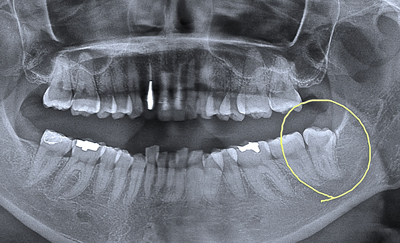

30代の女性。遠方より。主訴は「親知らずが、下あごの骨に引っかかっているらしい。難しい抜歯になりそうなので、かかりつけの医院では『抜けない』と言われた。出来れば今日、抜いて欲しい」でした。

局部的レントゲン画像を撮影して、親知らずと骨の引っかかり程度をチェック。

「特に問題はない」と判断したため、昼休みを使って抜歯をおこなうことに急遽決定。

15分程で抜けると予想をしていましたが、30分を過ぎても歯はビクともせず。

患者様は、顎関節症でもあったため、大きく口を開けることが出来ません。顎関節の痛みも発症、休憩を繰り返しながらも抜歯は続く。患者様の目からは苦痛の涙が…。

手を替え品を替え、抜歯開始から1時間後、ようやく私の抜歯鉗子(ペンチ様)から凄い形をした親知らずの歯が折れることなく出てきました。

参りました〜凄い形の親知らず